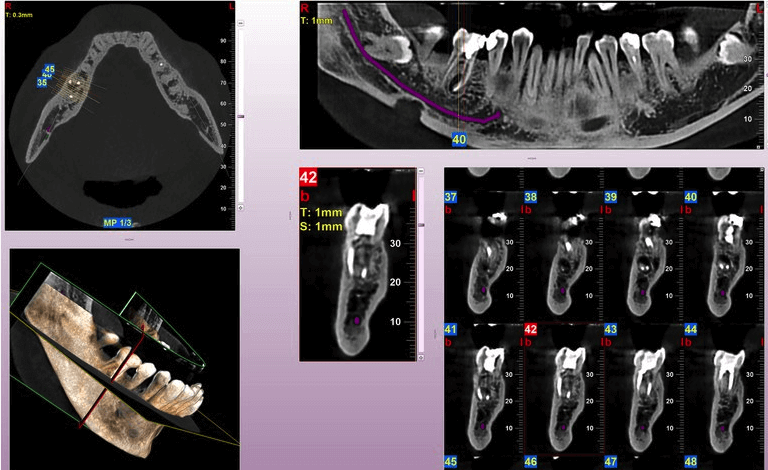

Сьогодні практично будь - яка стоматологічна процедура вимагає постановки чіткого діагнозу на основі даних, отриманих на точному і безпечному для пацієнта діагностичному обладнанні. Наша практика є першою у місті Самбір, яка обладнана сучасним комп’ютерним томографом MyRay Hyperion X9, що дозволяє за декілька хвилин отримати чітке та якісне 3D зображення. При тому, що апарат випромінює наднизьку дозу опромінення, а сам процес сканування триває 15 секунд.

За допомогою комп’ютерної томограми лікар отримує тривимірні знімки в різних площинах, а не тільки в одній, на відміну від звичного нам рентген зображення. Також у нашій клініці є можливість зробити панорамний знімок зубів.